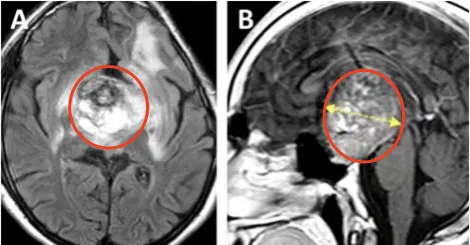

更加可怕的是,在随后的12年里,男孩的胶质瘤复发并在不断生长着,直到他长成一名16岁少年,肿瘤体积竟足足有68.1mm³,深度达到44.4mm!如此巨瘤,已经让少年苦不堪言,更何况他还出现了全垂体功能减退和严重的左侧视力障碍,几乎等同于失明。

术前情况:MRI显示鞍区、丘脑巨大肿瘤,归类为Bcentral病变的复发性毛细胞星形细胞瘤,侵犯累及左侧海马旁回和侧脑室的上部。肿瘤体积达68.1mm³,其深度为44.4mm,侧面角为21.9°。